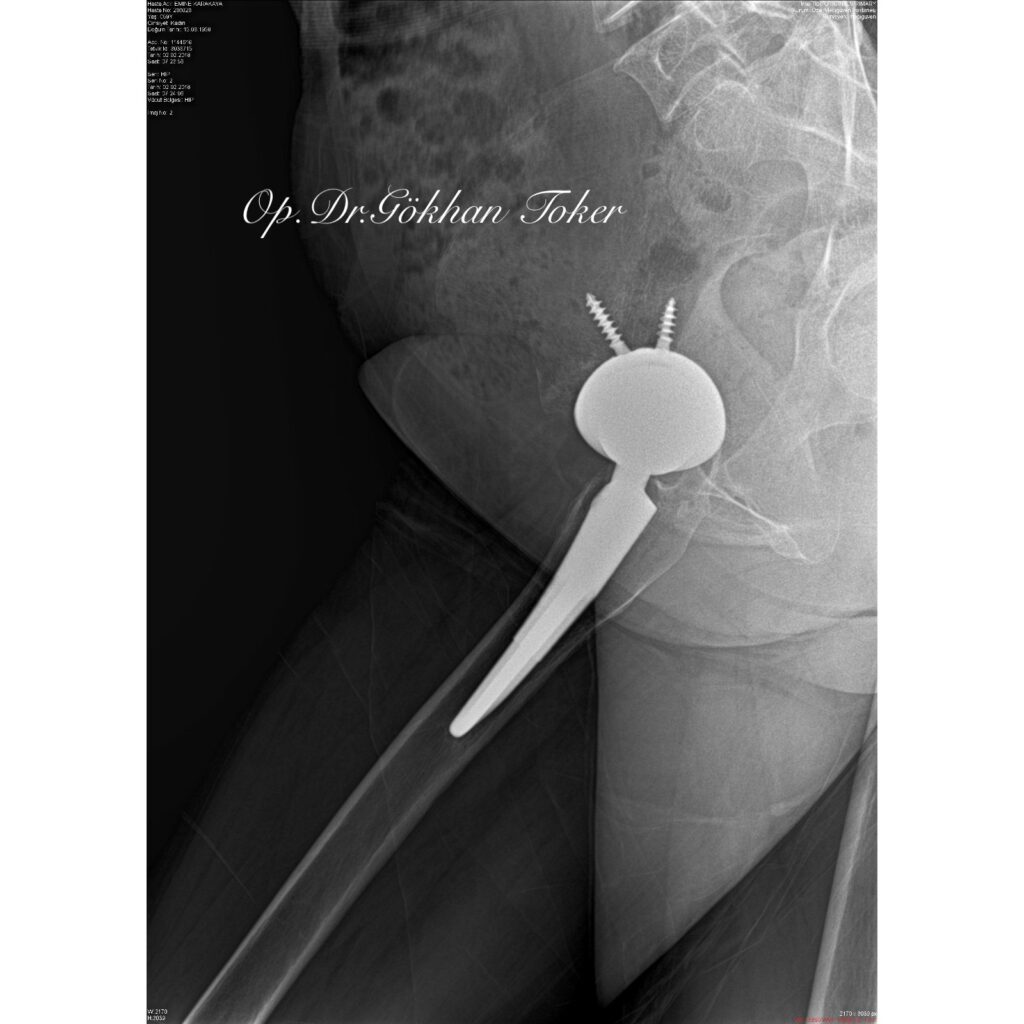

E.K.